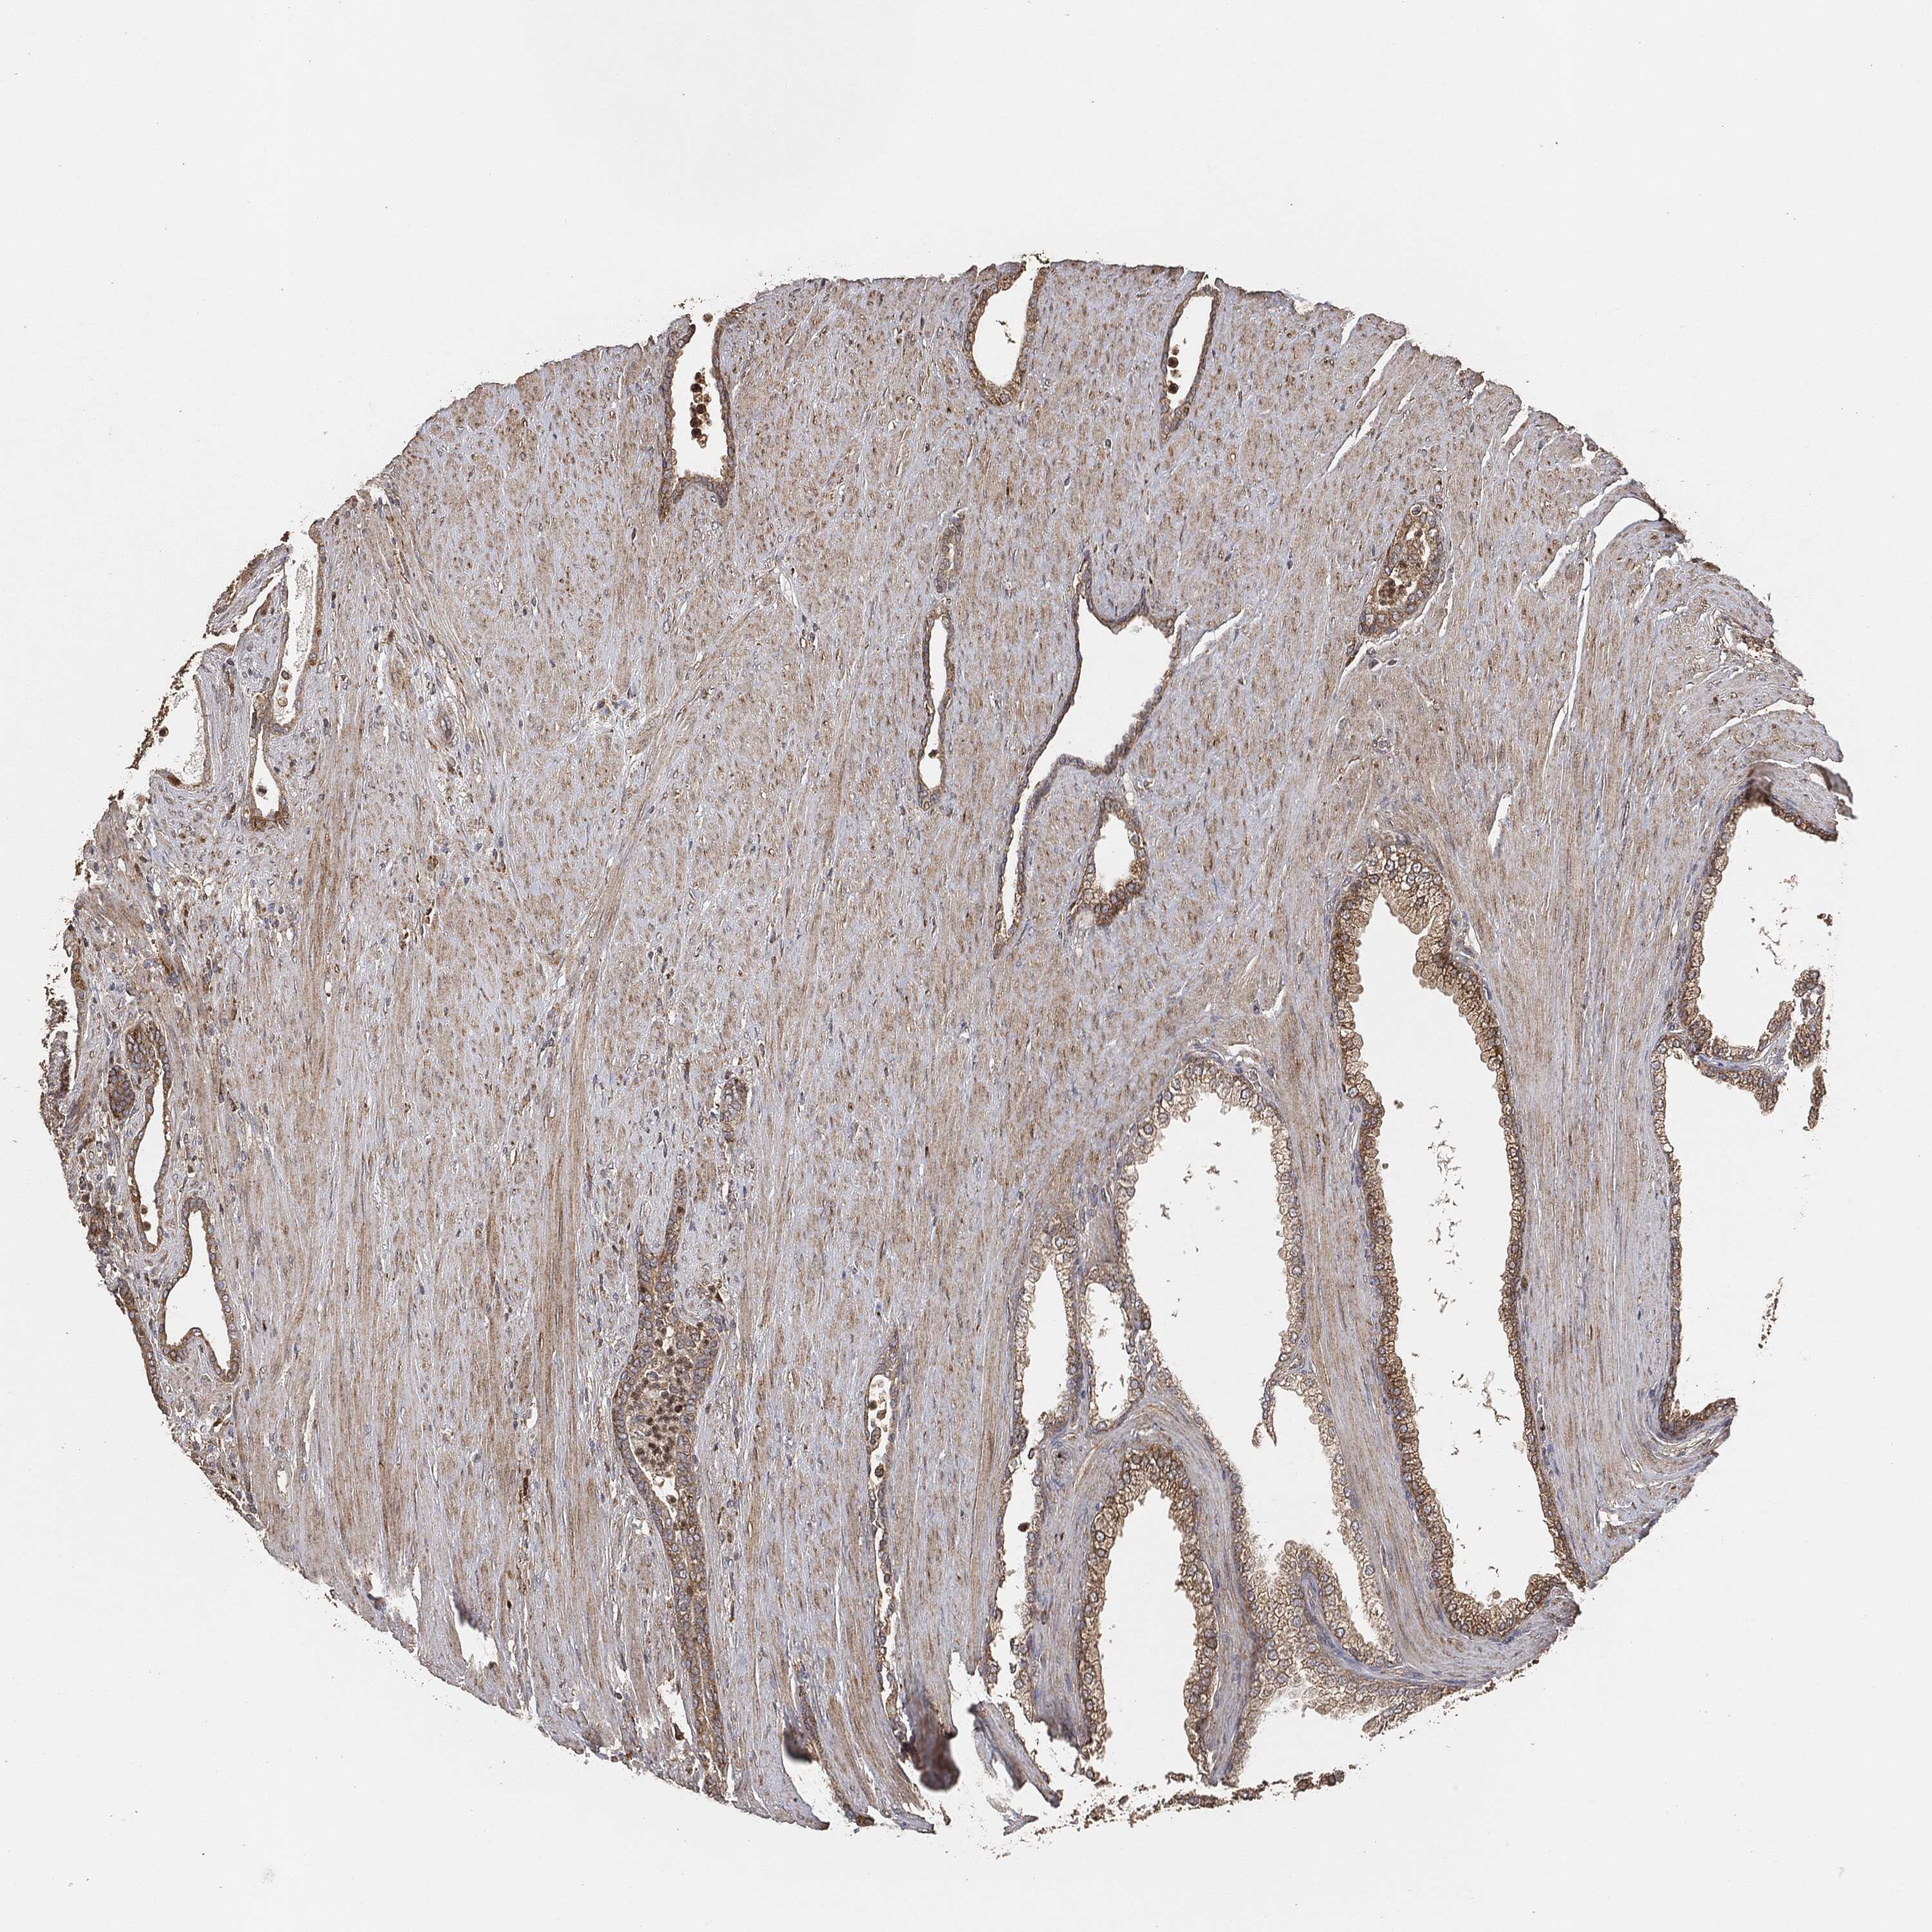

PROSTATE CANCER - Protein expressioni

A mouse-over function shows sample information and annotation data. Click on an image to view it in a full screen mode. Samples can be filtered based on level of antibody staining by selecting one or several of the following categories: high, medium, low and not detected. The assay and annotation is described here.

Antibody stainingi

Antibody staining in the annotated cell types in the current human tissue is reported as not detected, low, medium, or high, based on conventional immunohistochemistry profiling in selected tissues. This score is based on the combination of the staining intensity and fraction of stained cells.

Each image is clickable and will lead to virtual microscopy that enables deeper exploration of all samples and also displays staining intensity scores, fraction scores and subcellular localization as well as patient and tissue information for each sample.

Adenocarcinoma, Medium grade

Adenocarcinoma, Low grade

Adenocarcinoma, High grade

Adenocarcinoma, NOS